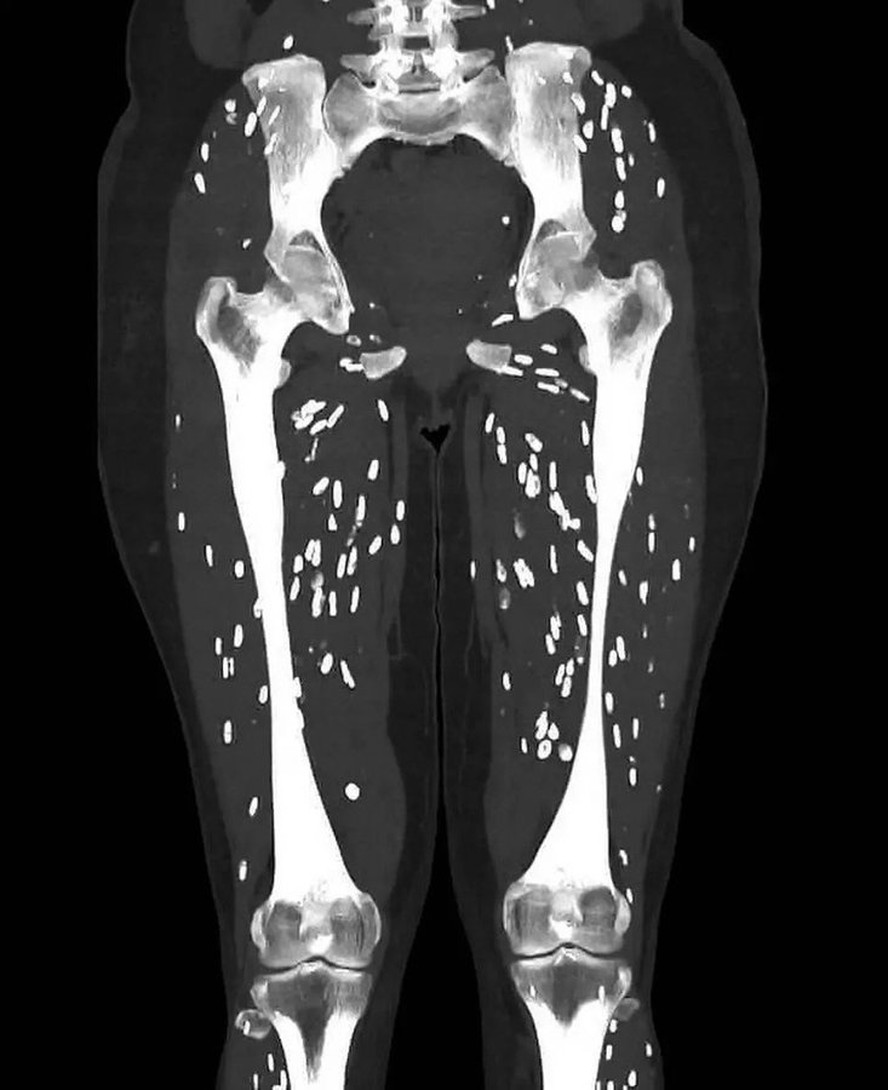

Com mais de seis milhões de visualizações,o médico de atendimento de urgência da Universidade da Flórida Sam Ghali usou uma publicação no X para falar sobre o risco de exposição à cisticercose pelo consumo de carne de porco mal cozida. A doença parasitária ocorre pelo contato com fezes humanas infectadas com o ovo da tênia através de alimentos,água ou superfícies contaminadas com fezes. Os humanos engolem os ovos quando comem alimentos contaminados ou colocam os dedos contaminados na boca.

Na postagem,Ghali diz que a imagem anexada é de um dos exames mais inacreditáveis que ele já viu. O médico aproveita para compartilhar com seus seguidores mais detalhes do processo de infecção,sintomas comuns e o que pode ocorrer em caso de negligência. Veja a publicação abaixo:

"Os humanos são infectados ao ingerir cistos que podem ser encontrados em carne de porco mal cozida. Após várias semanas (geralmente em torno de 5 a 12),esses cistos evoluem dentro do trato gastrointestinal para tênias adultas maduras. Essa condição é conhecida como Teníase Intestinal. Essas tênias adultas então eliminam ovos excretados nas fezes humanas. Depois que os ovos são ingeridos (humanos ou porcos),eles liberam larvas que penetram na parede intestinal e invadem a corrente sanguínea e de lá podem se espalhar para literalmente qualquer lugar do corpo inteiro. O cérebro,os olhos,os tecidos subcutâneos e os músculos esqueléticos são os destinos mais comuns. As larvas se alojam onde quer que acabem e,por fim,formam cistos conhecidos como cisticercos",detalhou Ghali.